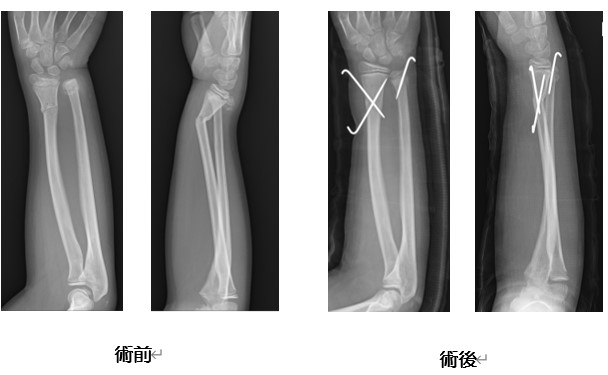

小児骨折

可能な限り、早期(受傷当日あるいは翌日)に手術を行っています。